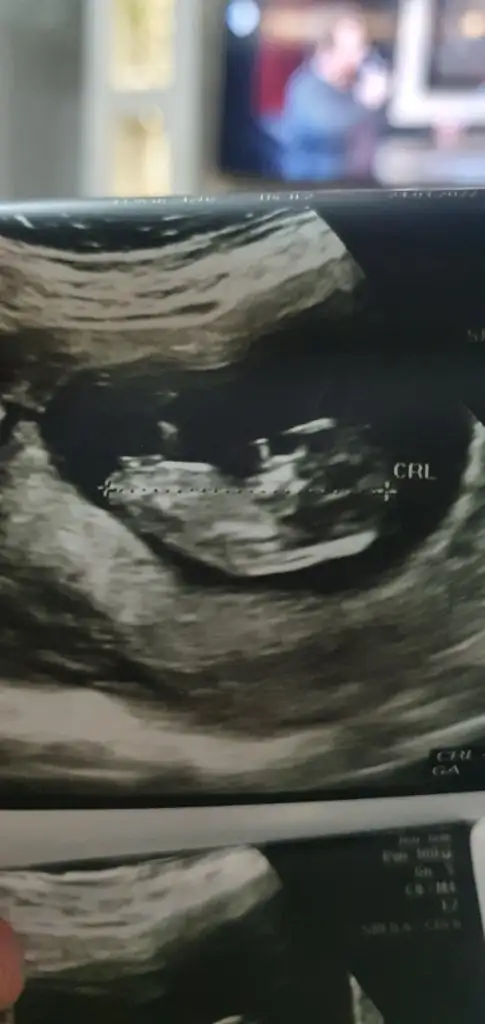

Sabah da atmıştım ama görünmedi sanırım

12+6 yorumlarmısınız lütfennŞimdiden teşekkürler

• E2CA524A-7965-4CCF-99C3-18C19DCAA4C1.webp

25,3 KB · Görüntüleme: 60